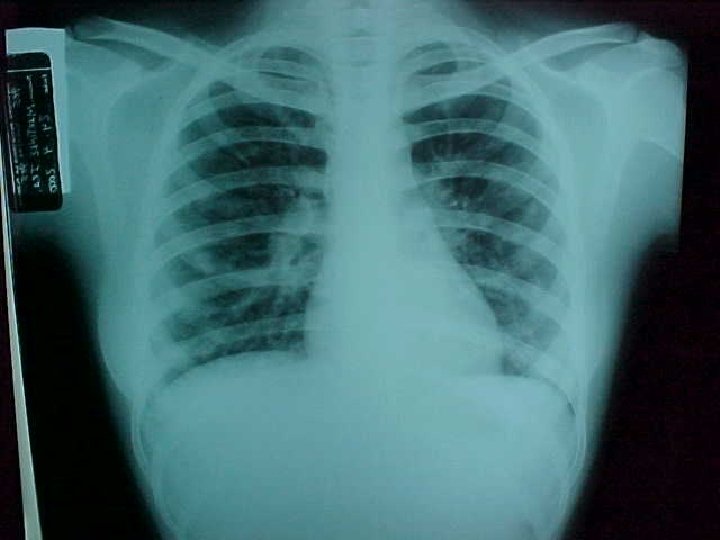

Histoplasmosis asociada a cueva en Venezuela Resultados: 28 estudiantes (17 hembras y 11 varones; rango de edad entre 15 -18 años con una media de 17 años) *20 (71. 4%) desarrollaron enfermedad aguda -64. 3% dentro de los 10 -28 días (mediana 14 días) posterior a la exposición. *2 (7. 1%) asintomáticos, tuvieron alteraciones radiológicas y en la serología para histoplasmosis.

Histoplasmosis asociada a cueva en Venezuela Resultados: 20 estudiantes enfermos-síntomas *Fiebre (77. 7%) *Dolor abdominal (38. 8%) *Tos no productiva (72. 2%) *Astenia (33. 3%) *Cefalea (66. 6%) *Dolor torácico (22. 2%) *Nauseas y vómitos (50%) *Disnea (16. 6%) *Rash (38. 8%) *Mialgias (16. 6%) *Eritema Nodoso (5. 5%)

Histoplasmosis asociada a cueva en Venezuela Resultados: *46. 4% de los 28 estudiantes y el 65% de aquellos que desarrollaron anormalidades clínicas o de laboratorio mostraron un test de inmunodifusión doble en gel específico positivo dentro de las siguientes 6 -12 semanas.

Histoplasmosis asociada a cueva en Venezuela Resultados: *7 pacientes recibieron tratamiento ambulatorio con Itraconazol VO 200 mg/día por 4 -6 semanas, debido a la severidad y/o persistencia de las manifestaciones clínicas originales, o el desarrollo de complicaciones, con remisión completa de los síntomas en las primeras dos semanas de tratamiento